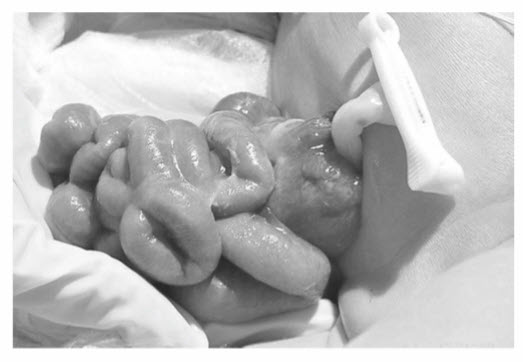

The defect in gastroschisis is:

A. To the left of the umbilicus

B. To the right of the umbilicus

C. Through the umbilicus

D. Superior to the umbilicus